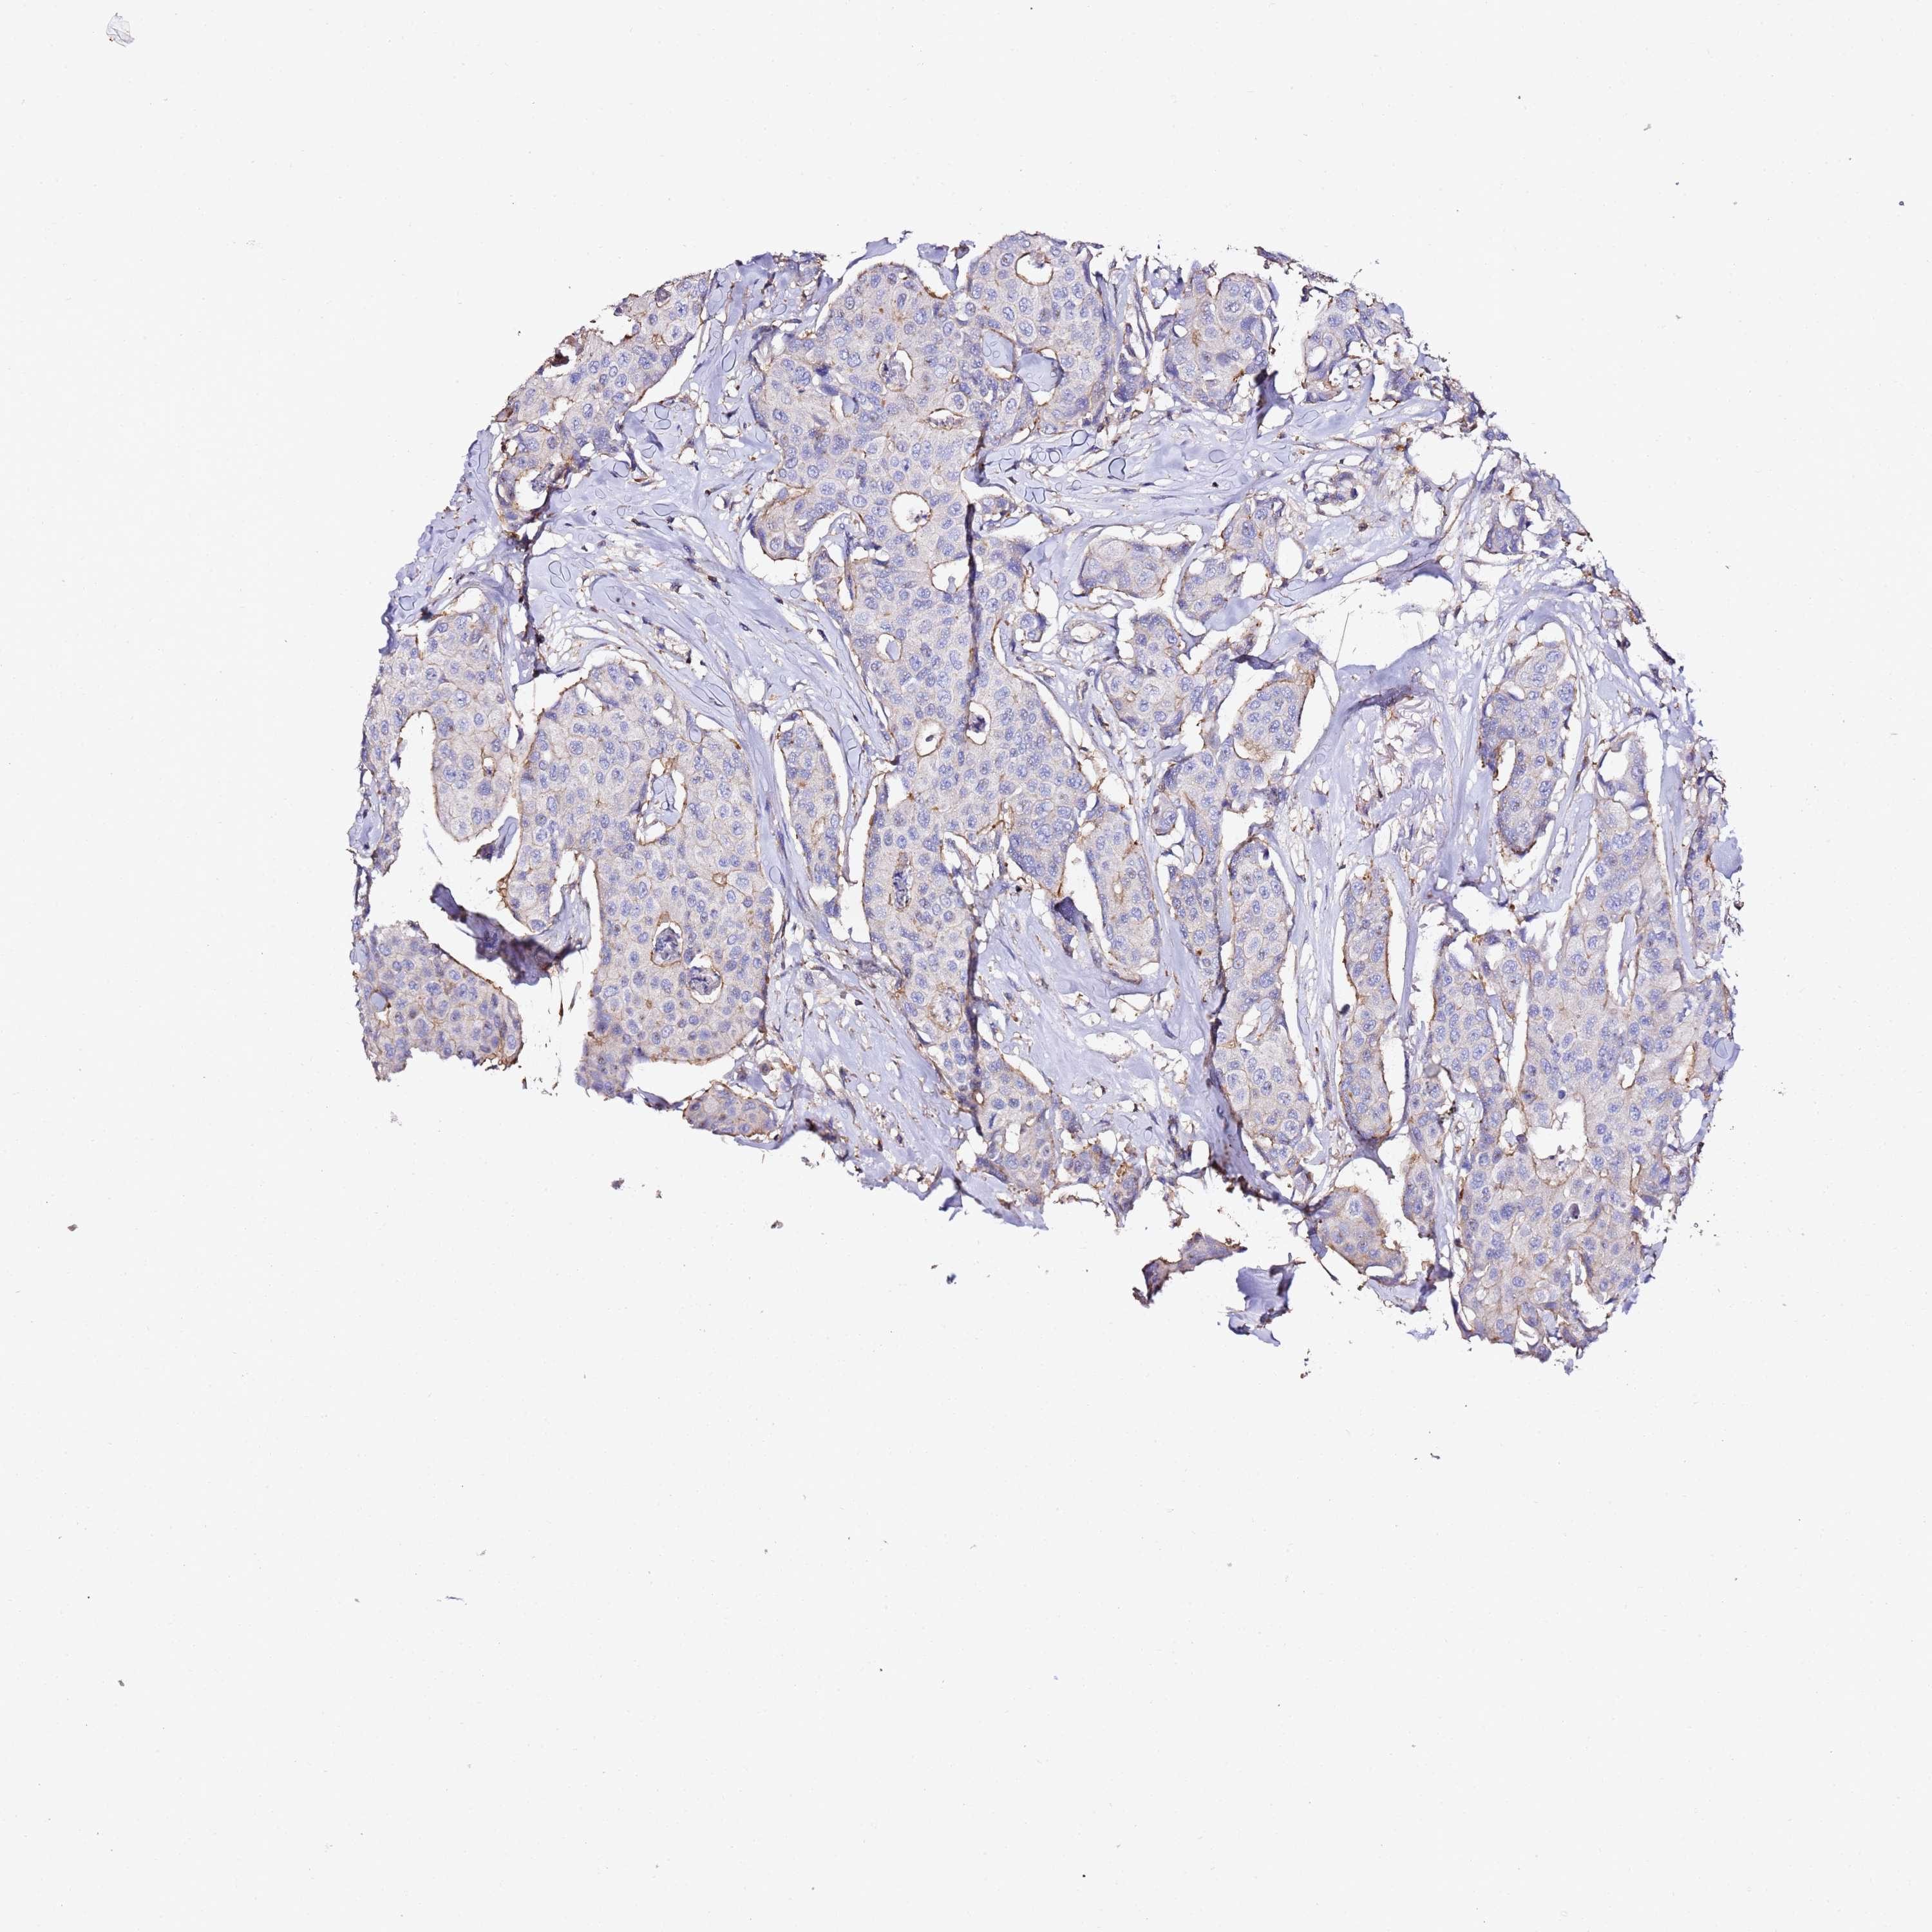

CANCER BREAST CANCER Show tissue menu

Breast cancer

Human cancer